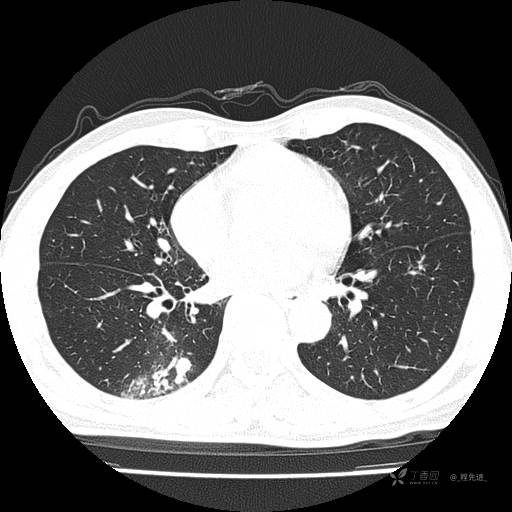

2月特别精彩病例|咳嗽、咳痰20余天,典型病例分享【结果已公布】

患者年龄:51岁

主诉:咳嗽、咳痰20余天

简要病史:20余天前开始出现咳嗽、咳痰症状,阵发性刺激性咳,白色粘痰,不易咳出,无发热,无咯血,无恶心、呕吐等不适,未诊治,咳嗽、咳痰症状持续存在。

体格检查:T:36.3 ℃ P:79 次/分 R:20 次/分 BP:128/64 mmHg,神志清楚,呼吸平稳,双肺呼吸音粗,右下肺闻及细湿性啰音。心率79次/分,节律整齐,各瓣膜听诊区未闻及病理性杂音。腹部未见异常,双下肢无水肿。

辅助检查:我院门诊胸部CT示:如下。心电图:窦性心律;正常心电图。